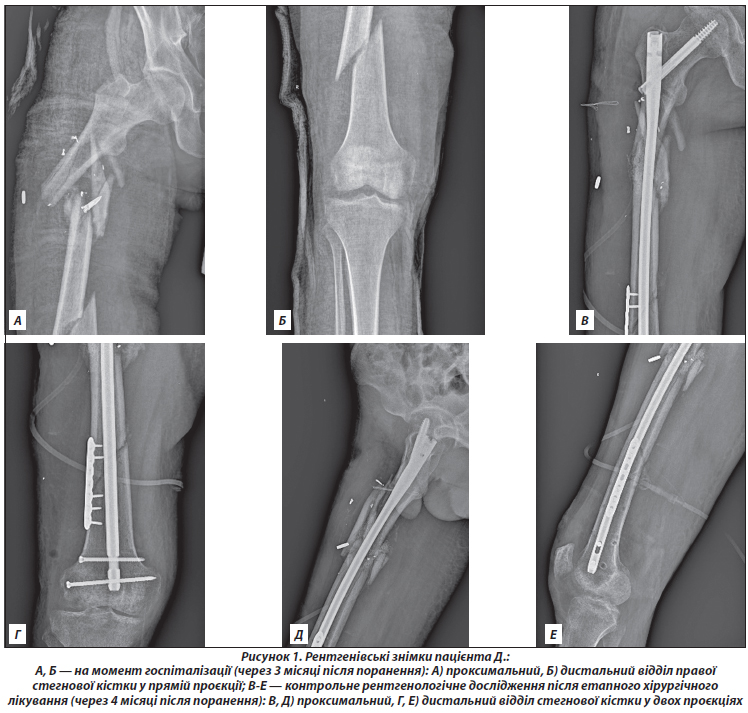

Клінічний випадок 2. Пацієнт Г., 32 роки. Вогнепальне осколкове поранення (18.03.2022), неправильно консолідований вогнепальний перелом обох кісток верхньої третини правої гомілки зі зміщенням. Перебував у полоні. Госпіталізований через майже через 4 місяці після отримання поранення. За час полону медичну допомогу не отримував, за винятком первинної обробки рани. Перебував на вимушеному ліжковому режимі, на нижню кінцівку не спирався. Обстеження кісткової тканини проведено після стабілізації соматичного стану й проведення багатоетапного хірургічного лікування через 4 міс. після травми (рис. 2).

Клінічний випадок 3. Пацієнт Б., 22 роки. Вогнепальне осколкове поранення (07.04.2022) лівого стегна, багатоуламковий неправильно консолідований перелом верхньої третини лівої стегнової кістки зі зміщенням відламків. Інфікована рана латеральної поверхні лівого стегна. Після поранення пацієнт перебував у полоні. Госпіталізований через 4 місяці у вкрай тяжкому стані з ознаками кахексії — втрата маси тіла близько 25 кг. Після етапних оперативних втручань і стабілізації соматичного стану виконано обстеження кісткової тканини (рис. 3).

/17.jpg)